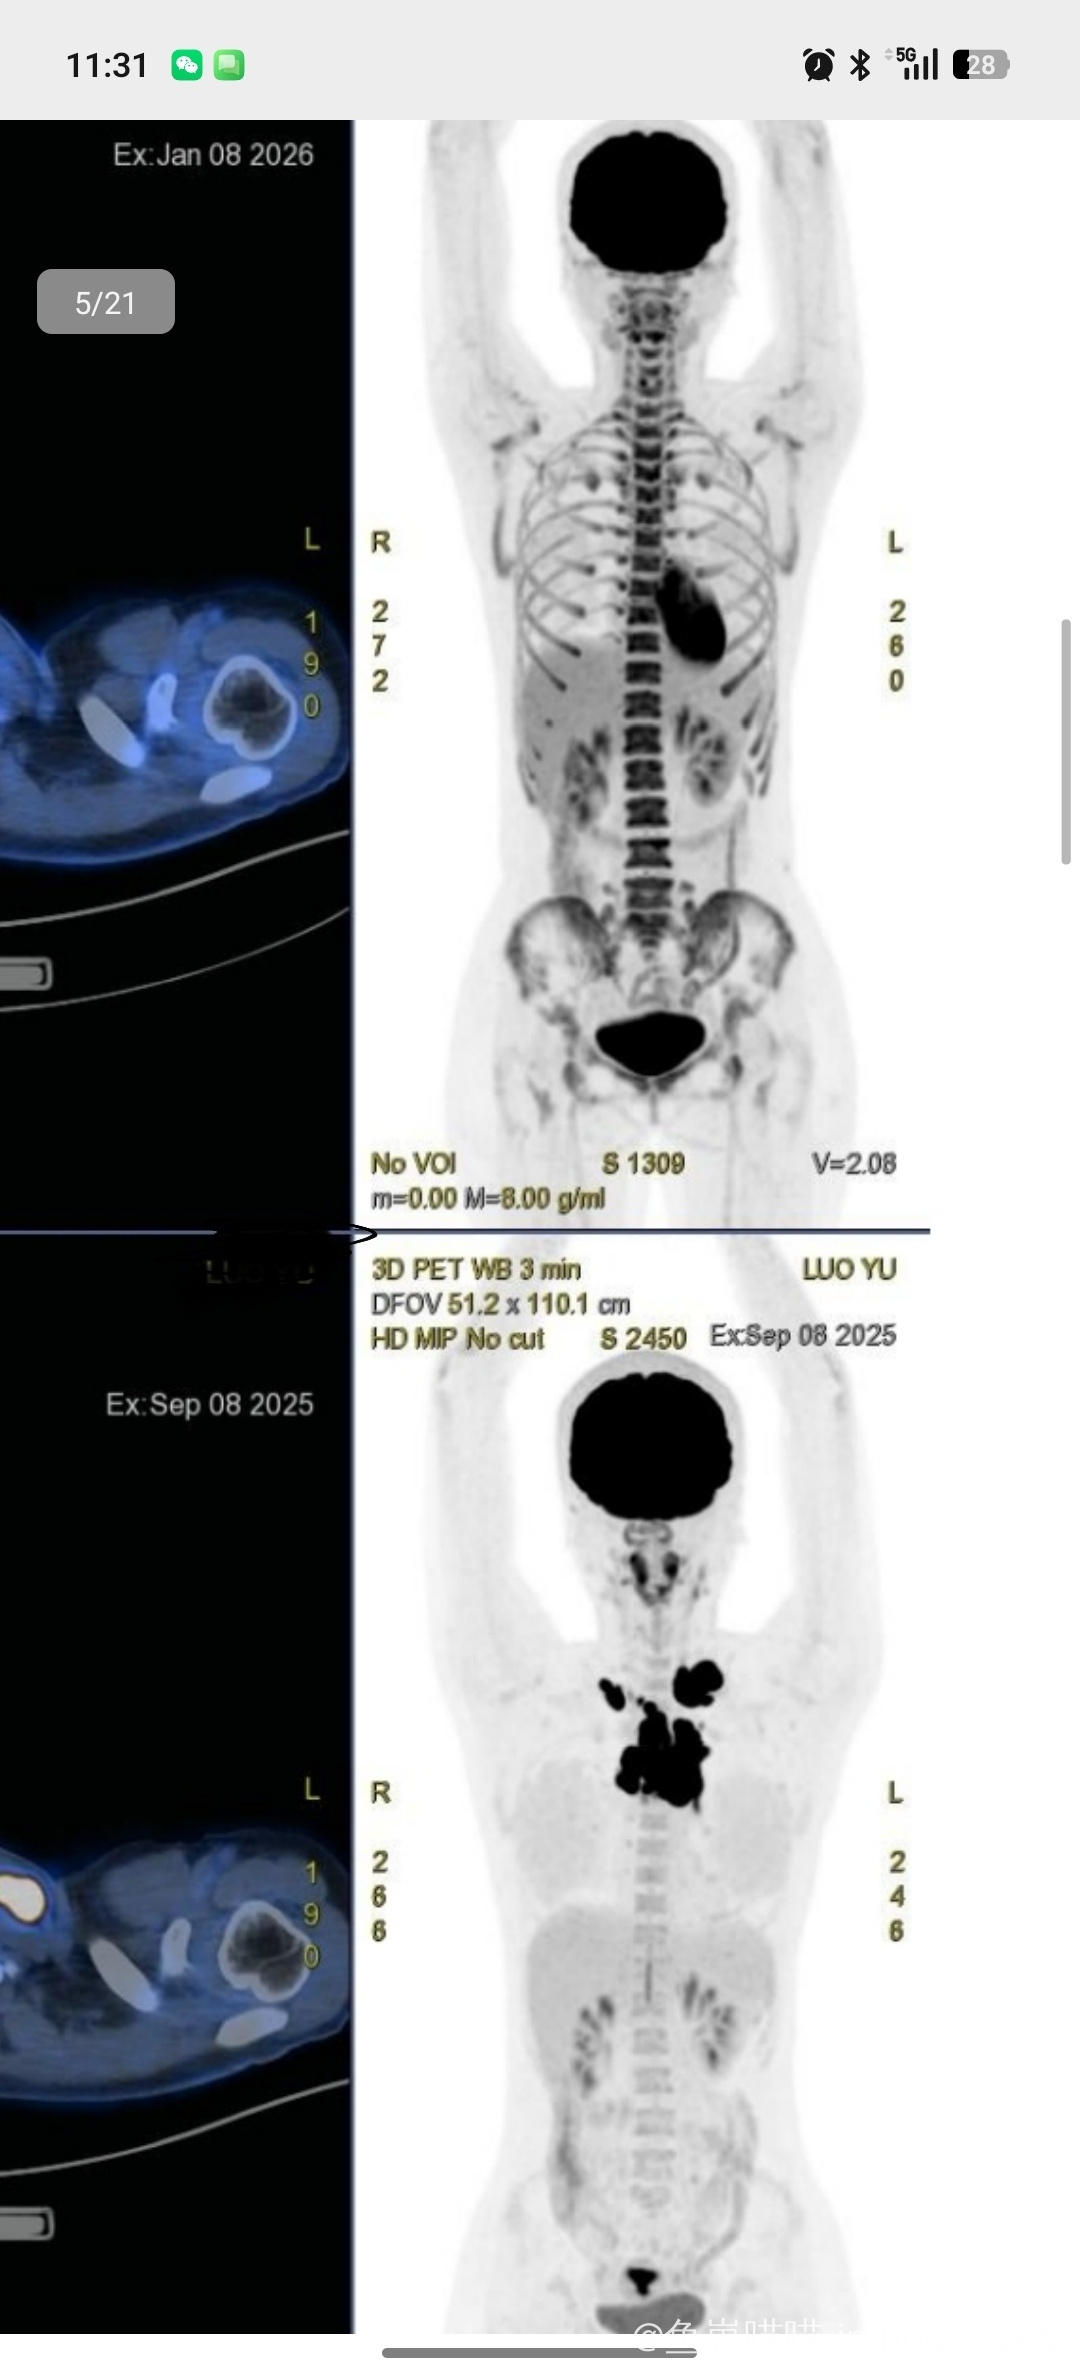

病情与治疗相关情况说明:性别女,年龄24岁,2025年9月确诊弥漫大B细胞淋巴瘤(二期,non-GCB分型),IPI评分1分,无骨髓侵犯。

1. 一疗前PET-CT:肿瘤主要累及双锁骨及纵隔区域,纵隔最大病灶约7.4cm×4.6cm,suvmax:34.0。

2. 二疗后增强CT:前纵隔见边界不清片状影,范围约38mm×13mm,轻度强化;双侧锁骨上区见数个淋巴结,左侧大者短径约7mm,不均匀强化。

3. 四疗后PET-CT:前纵隔小片软组织影,放射性分布略浓密(SUV约2.8),范围约1.6×1.2cm,多维尔评分:3分;双锁上及纵隔小淋巴结代谢无异常。